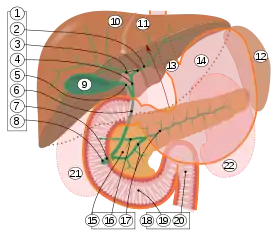

9. Gallbladder.

10–11. Right and left lobes of liver.

12. Spleen.

13. Esophagus.

14. Stomach.

15. Pancreas: 16. Accessory pancreatic duct, 17. Pancreatic duct.

18. Small intestine: 19. Duodenum, 20. Jejunum

21–22. Right and left kidneys.

The front border of the liver has been lifted up (brown arrow).[3]